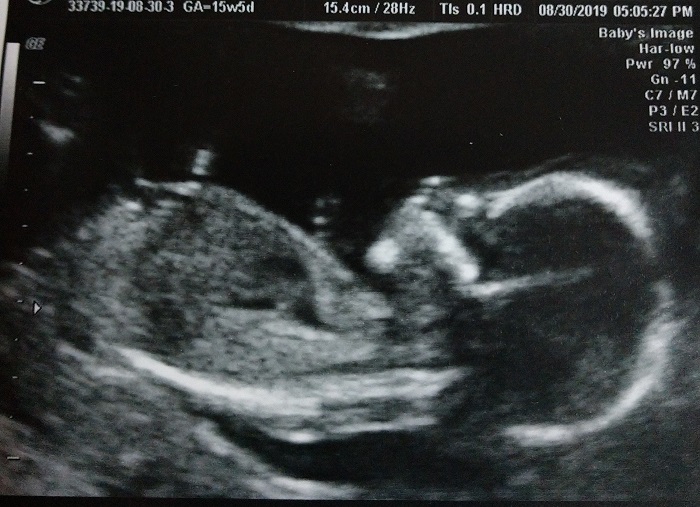

It has only been a few weeks since the last ultrasound, but I was really amazed at how much bigger the baby was. Baby was VERY active Friday and seemed to keep flipping around as the tech tried to get good pictures. In one picture, we were able to see the baby’s foot. Then we were able to see the profile.

Then we were able to hear the baby’s heartbeat again. This is one of those wonderful sounds that I just love to hear.

The baby’s heart rate was 150. At the last ultrasound, the heart rate was 159-160. Our OB stated that if he had to guess, he’d say we were having a girl. Today, we’d find out if he was right.